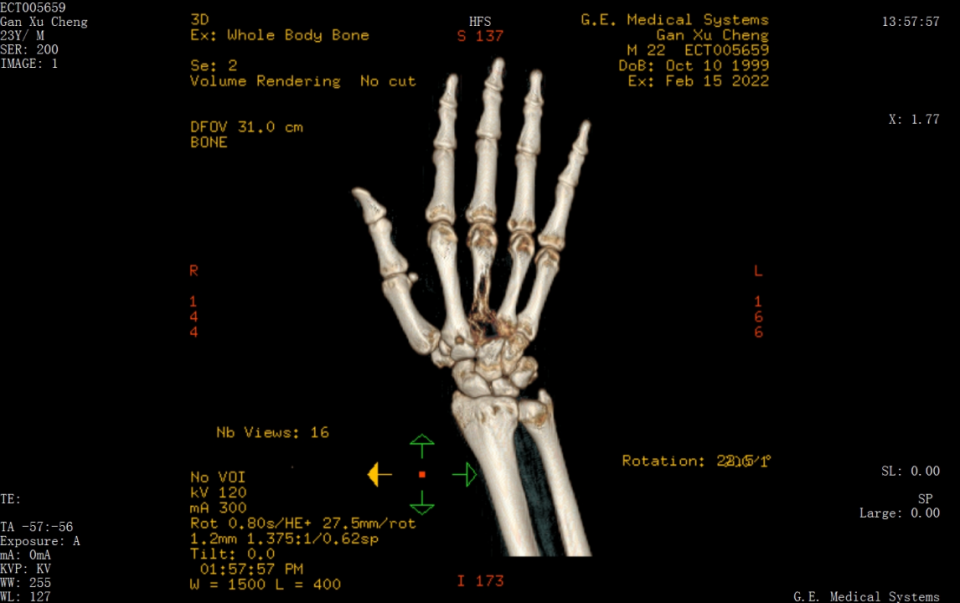

全身骨显像 SPECT/CT 融合图像:CT 示右第 3 掌骨膨大,不同程度骨质破坏,病变累及第 4 掌骨近端,周围软组织明显肿胀。

结论考虑右第 3 掌骨及第 4 掌骨近端原发性骨肿瘤(骨肉瘤?),建议病理活检。

图片图 4 患者 SPECT/CT 融合图像显示右第 3 掌骨膨大,不同程度骨质破坏,病变累及第 4 掌骨近端